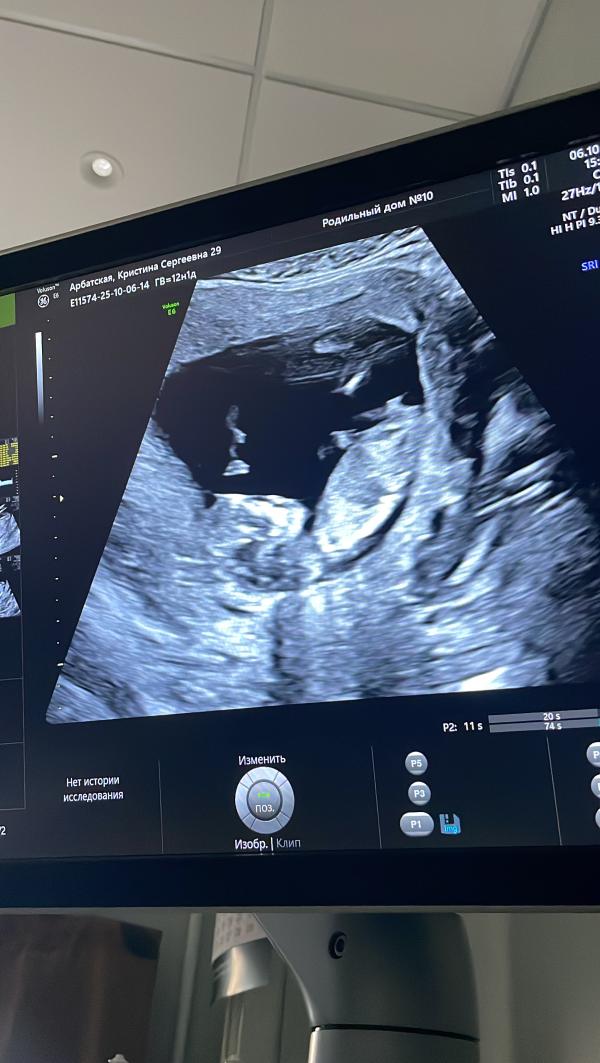

А теперь нам уже 14 недель, мы растём.